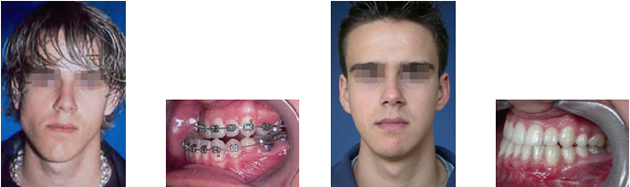

Пациент с преразвитие на долната челюст (мандибуларен прогнатизъм) – преди и след реконструкция на долната челюст - случай на доц. Джоров.

Лечението на челюстно-лицевите деформации е обект на ортогнатичната лицево-челюстна хирургия. Предварително чрез ортодонтско лечение трябва да се координира размера на долната и горна зъбна дъга, за да ги подготви за функционална и стабилна захапка след операцията. Съвременните хирургични методи и средства за фиксация, съкращават времето за обездвижване на челюстите. Разрезите и достъпите през устата не оставят никакви видими белези. Постига се оптимално възстановяване на функцията и хармонията на лицето.